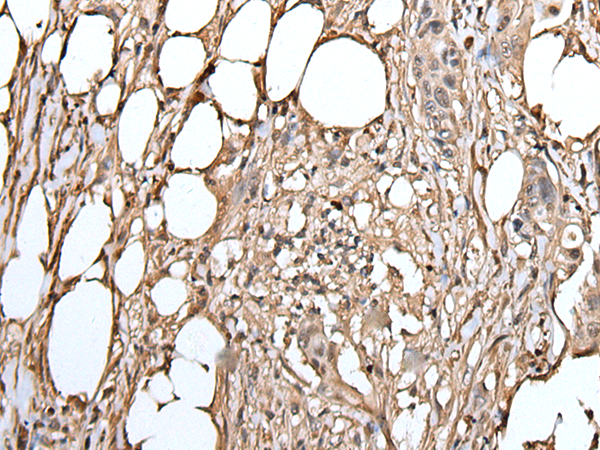

IHC (Immunohistochemistry)

(The image on the left is immunohistochemistry of paraffin-embedded Human liver cancer tissue using ATAD1 Antibody at dilution 1/100, on the right is treated with fusion protein. (Original magnification: x200))